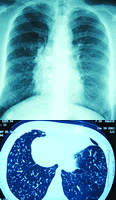

血常规、肝肾功、血浆凝血酶原时间及活动度(PT+A)、血沉(ESR)、C反应蛋白(CRP)、抗核抗体(ANA)均正常;支原体、衣原体抗体(-),结核菌纯蛋白衍生物(PPD)皮试(-),抗结核菌抗体(TB-Ab)(-),冷凝集试验(-)。铁三项:血清铁(SI )38~116 μg/dl(正常值70~150 μg/dl),总铁结合力(TIBC) 463~470 μg/dl(正常值200~400 μg/dl),转铁蛋白饱合度(TS) 8%~25%(正常值25%~35%),血清铁蛋白(SF) 8~17 ng/L(正常值>14.0 ng/L)。X线胸片(图1)和胸部CT(图2)示:双肺多发结节影(以双下肺为著),纵隔淋巴结大,右肺中上叶支扩合并感染,右肺下叶胸膜下见大泡。鼻窦CT示:双侧上颌窦炎。多次痰培养:有铜绿假单胞菌、白念珠菌、青霉菌及肺炎链球菌。